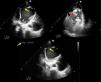

Imágenes en Medicina Intensiva

Shock cardiogénico por gran pseudoaneurisma apical del ventrículo izquierdo: una complicación infrecuente

Cardiogenic shock due to a large apical pseudoaneurysm of the left ventricle: A rare complication